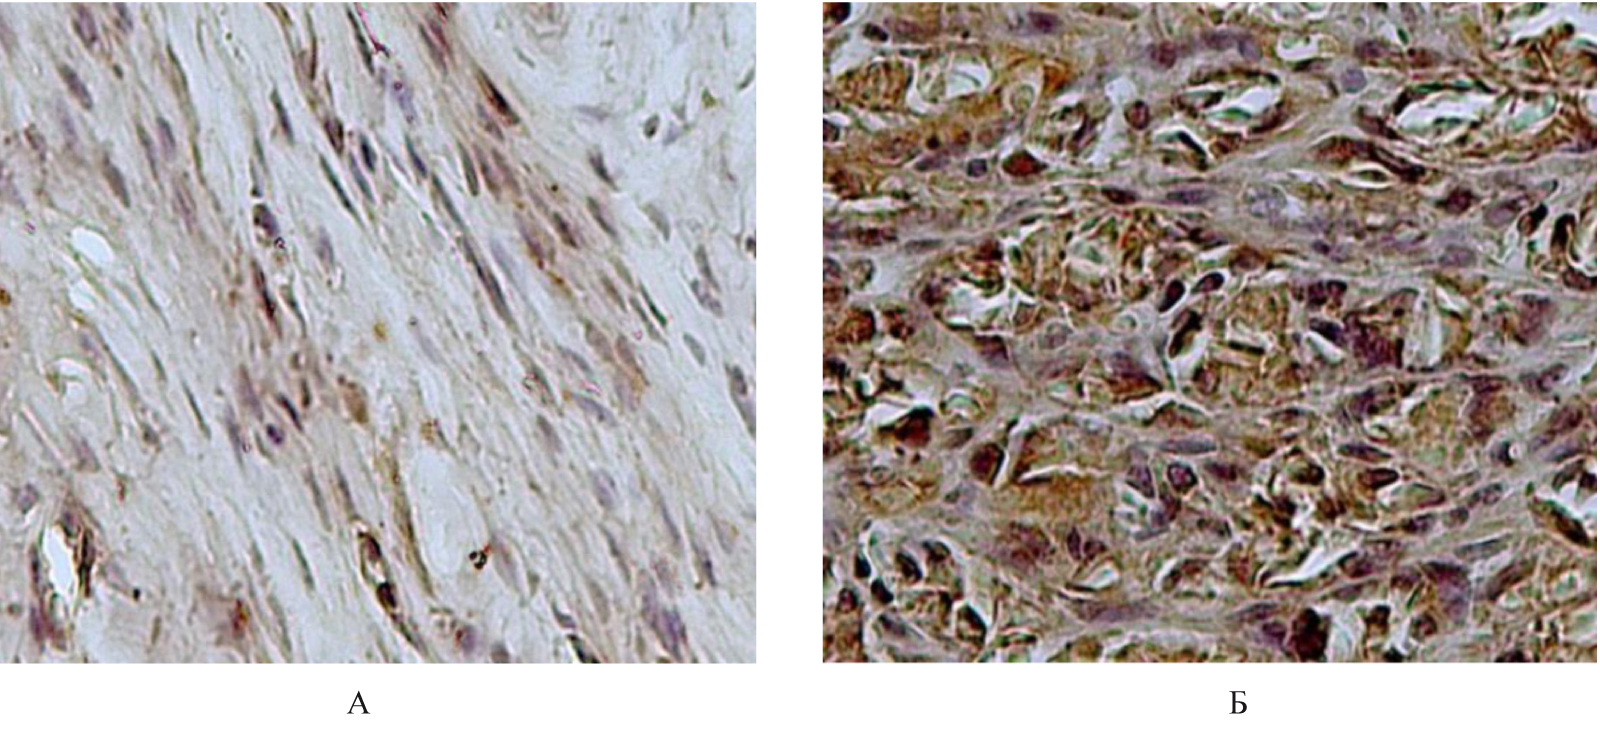

В исследовании образцов тканей из Г5 с использованием антител против МПП1, МПП19 в цитоплазме фибробластов и фиброцитов наблюдалась слабо выраженная экспрессии ИРМ (1 балл). При использовании антител против МПП9 в цитоплазме фибробластов и фиброцитов иммунонегативной реакции не определяли (0 баллов). В единичных клетках воспалительного инфильтрата имела место умеренно выраженная цитоплазматическая экспрессия ИРМ (2 балла), но при использовании антител к ТИМП1 отмечалась слабо выраженная цитоплазматическая экспрессия ИРМ (1 балл) (рис. 3).

Рис. 3. Гистологическое строение сухожилия крысы из группы 1: А – иммуногистохимическое исследование антитела против MMP1, докраска гематоксилином Карацци (ув. × 400), Б – иммуногистохимическое исследование антитела против MMP9, докраска гематоксилином (ув. × 400)